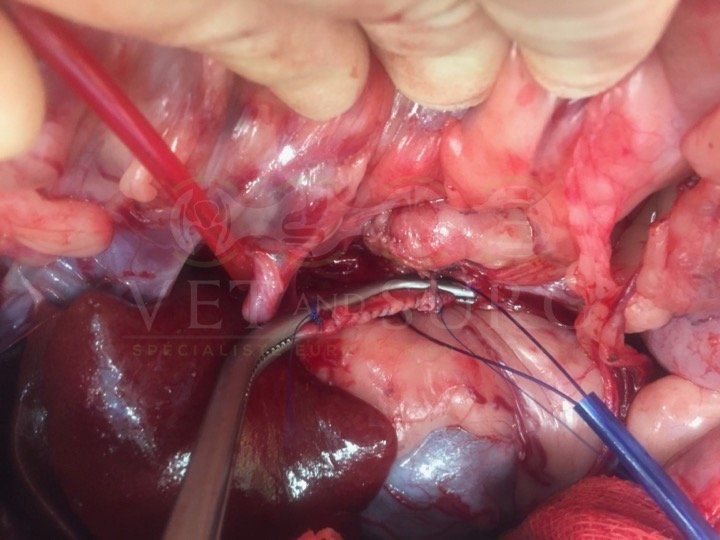

Obstruction urétérale chez un chat Sacré de birmanie de 8 ans

Une pose de SUB a été effectuée, reliant la cavité pyélique gauche à la vessie, en court-circuitant l'uretère obstrué.